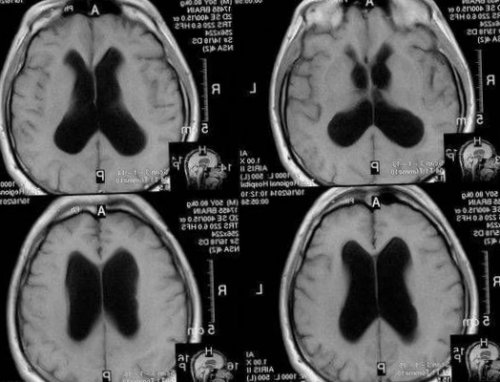

Чтобы опровергнуть или подтвердить сомнительный диагноз, можно пройти обследования на аппарате МРТ, которое покажет все возможные новообразования, их размеры и содержимое, что позволит судить о нарастании давления внутри черепа.

и признакиС целью оттока • петлевые диуретики;облегчения общего состояния Лечебные мероприятия зависят • длительности развития заболевания;Нейрохирурги для лечения гидроцефалии у взрослых применяют малотравматичную нейроэндоскопическую методику – эндоскопическую вентрикулоцистерностомию дна третьего желудочка. В желудочки мозга вводят хирургический инструмент с камерой на конце. С камеры изображение передаётся на монитор, что позволяет точно контролировать все манипуляции. На дне третьего желудочка создают дополнительное отверстие, соединяющееся с цистернами основания мозга. Так восстанавливается физиологический отток ликвора между желудочками и цистернами.Как лечить гидроцефалию головного мозга у взрослых? Начальные стадии гидроцефалии неврологи Юсуповской больницы лечат медикаментозно.• ультразвуковое исследование сосудов головного мозга для определения состояния артериального и венозного кровотока.Врачи Юсуповской больницы проводят диагностику гидроцефалии с помощью компьютерной и магнитно-резонансной томографии. Эти методы позволяют определить размеры и форму желудочков, цистерн мозга субарахноидального пространства. Если врачи клиники неврологии выявляют ранние признаки гидроцефалии на МРТ, они назначают медикаментозное лечение, позволяющее остановить прогрессирование болезни. Рентгенография цистерн основания мозга позволяет уточнить тип гидроцефалии и оценить направление тока ликвора.• быстрая утомляемость;Сообщающаяся гидроцефалия головного мозга у взрослых чаще имеет хроническое течение. Заболевание развивается постепенно, через несколько месяцев после воздействия провоцирующего фактора. Вначале нарушается цикличность сна, появляется сонливость или бессонница. У пациентов ухудшается память, появляется быстрая утомляемость, вялость. По мере прогрессирования заболевания когнитивные нарушения усугубляются вплоть до деменции. Пациенты ведут себя неадекватно и теряют способность к самообслуживанию.• посттравматических состояний и травм головного мозга.• опухолей желудочков и вещества мозга;• сосудистой патологии головного мозга (субарахноидальное и внутрижелудочковое кровоизлияние в результате разрыва неправильного соединения артериовенозных сосудов или аневризм);• гипотензивной (пониженное ликворное давление).